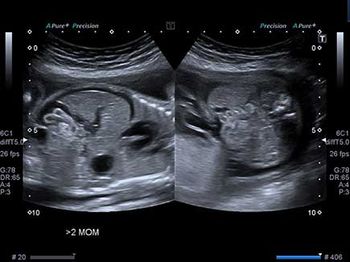

Challenge your diagnostic skills: Anything unusual about this fetal head?